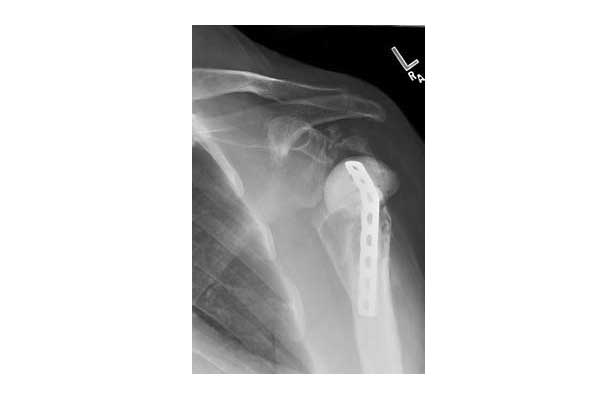

Η ανάστροφη αρθροπλαστική ώμου είναι μια νεότερη πρόθεση που χρησιμοποιεί μια “μη-ανατομική” φιλοσοφία για την αντικατάσταση της άρθρωσης σε εκείνους τους ασθενείς που πάσχουν από βαριά οστεοαρθρίτιδα και κακή λειτουργικότητα του στροφικού πετάλου μετά από μαζικές ρήξεις κ.α. Επιπλέον, αυτού του είδους η πρόθεση μπορεί να χρησιμοποιηθεί για αντικατάσταση της ολικής αρθροπλαστικής μετά από επιπλοκές όπως η χαλάρωση ή η λοίμωξη ή τέλος για σύνθετα κατάγματα σε ηλικιωμένους ασθενείς που δεν μπορούν να αντιμετωπιστούν με την μέθοδο της οστεοσύνθεσης λόγω οστικού ελλείμματος και κακής ποιότητας του εναπομείναντος οστού.

Στην ανάστροφη ολική αρθροπλαστική η κεφαλή του βραχιονίου (σφαίρα) αντικαθίσταται με μια κοίλη επιφάνεια (πολυαιθυλένιο), ενώ η κοιλότητα της ωμογλήνης αντικαθίσταται με μια μεταλλική σφαίρα. Αυτό δημιουργεί ένα σταθερό υπομόχλιο ώστε να μπορεί ο ασθενής να χρησιμοποιεί τον δελτοειδή για να ανυψώσει το χέρι του, χωρίς τη βοήθεια του στροφικού πετάλου. Η πρόθεση σταθεροποιείται στη θέση της με βίδες όσον αφορά στην ωμογλήνη και τσιμέντο ή με ενσφηνωμένο στυλεό (press-fit) όσον αφορά στο βραχιόνιο.

Στην ανάστροφη ολική αρθροπλαστική η κεφαλή του βραχιονίου (σφαίρα) αντικαθίσταται με μια κοίλη επιφάνεια (πολυαιθυλένιο), ενώ η κοιλότητα της ωμογλήνης αντικαθίσταται με μια μεταλλική σφαίρα.